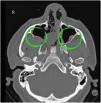

We report the surgical management of a spontaneous and recurrent nasal fistula using a temporoparietal fascial flap for definitive treatment after several failed attempts to close the fistula by conventional approaches. Two formalin-fixed cadaveric human heads were also dissected to study the anatomy and surgical technique involved in the design of the temporoparietal fascial flap.